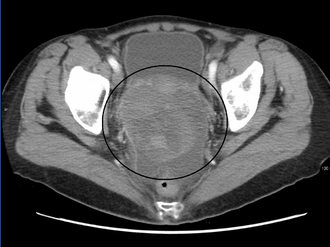

CT scanning is preferred to assess the extent of the tumor in the abdominopelvic cavity, though magnetic resonance imaging can also be used.[28] CT scanning can also be useful for finding omental caking or differentiating fluid from solid tumor in the abdomen, especially in low malignant potential tumors. However, it may not detect smaller tumors. Sometimes, a chest x-ray is used to detect metastases in the chest or pleural effusion. Another test for metastatic disease, though it is infrequently used, is a barium enema, which can show if the rectosigmoid colon is involved in the disease. Positron emission tomography, bone scans, and paracentesis are of limited use; in fact, paracentesis can cause metastases to form at the needle insertion site and may not provide useful results.[29] However, paracentesis can be used in cases where there is no pelvic mass and ascites is still present.[29] A physician suspecting ovarian cancer may also perform mammography or an endometrial biopsy (in the case of abnormal bleeding) to assess the possibility of breast malignancies and endometrial malignancy, respectively. Vaginal ultrasonography is often the first-line imaging study performed when an adnexal mass is found. Several characteristics of an adnexal mass indicate ovarian malignancy; they usually are solid, irregular, multilocular, and/or large; and they typically have papillary features, central vessels, and/or irregular internal septations.[31] However, SCST has no definitive characteristics on radiographic study.[33]